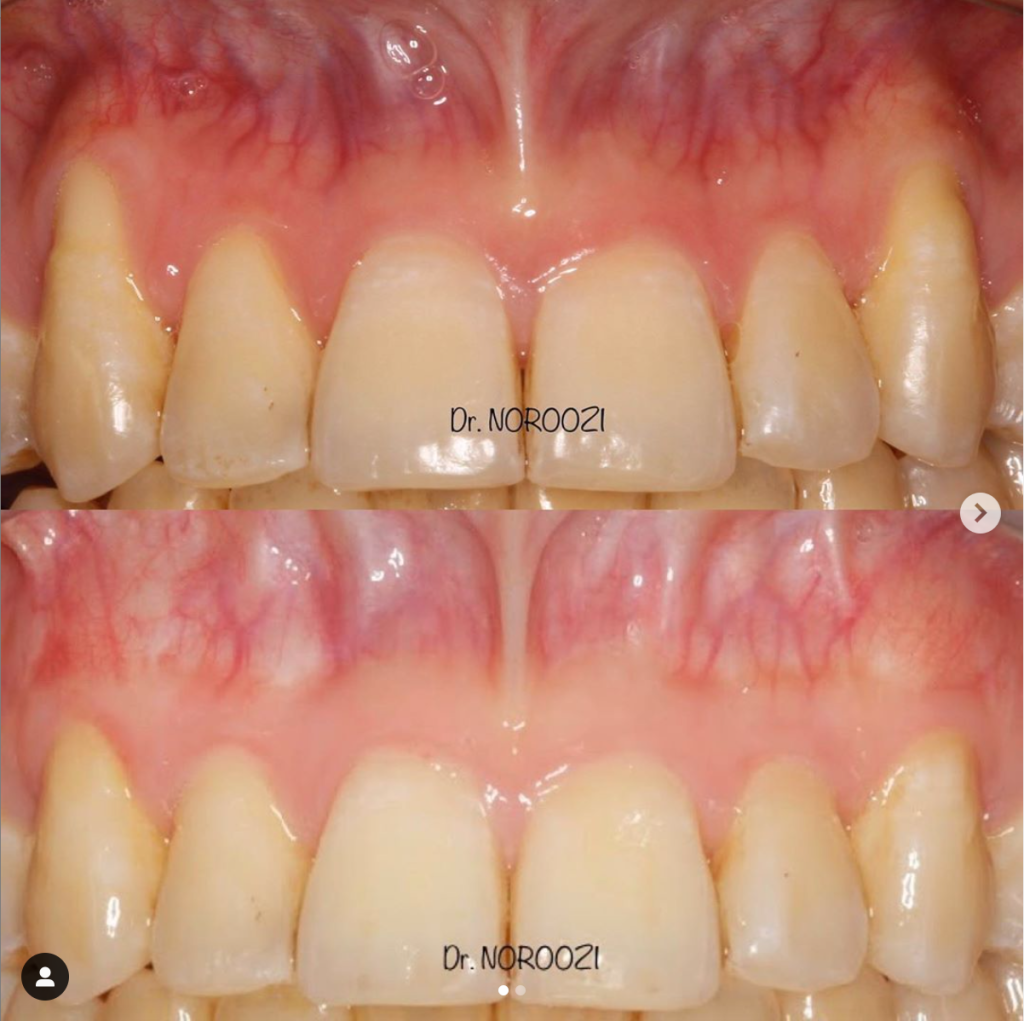

Gummy Smile Treatment- Lip Repositioning & Aesthetic Crown lengthening

Gummy Smile Treatment Esthetic Crown lengthening Dr. Noroozi IMPrESS Perio Implant Center Burnaby BC Vancouver Burnaby Periodontist